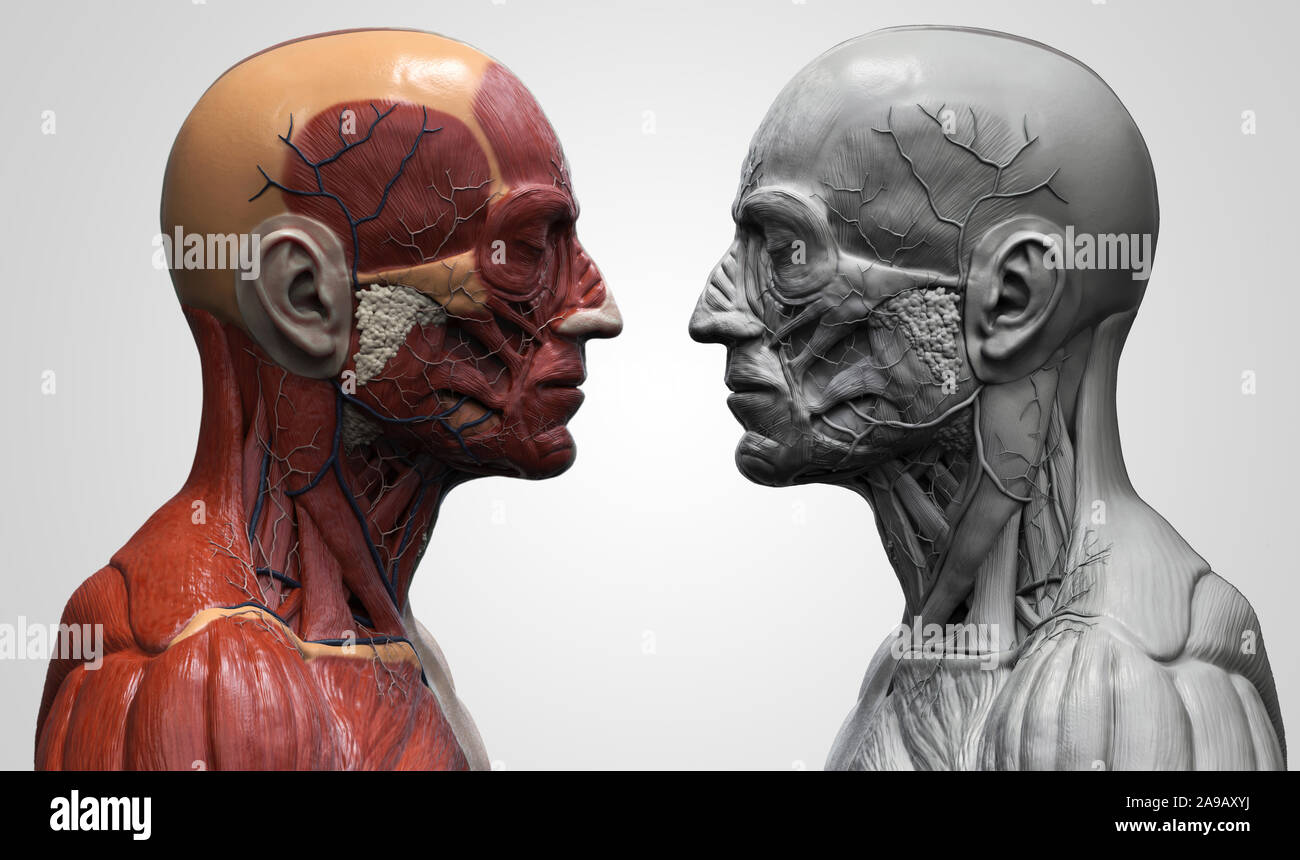

RF2A9AXYJ–Menschliche Körper Anatomie Muskeln Aufbau eines männlichen, Vorderansicht Seitenansicht und Perspektive, 3D-Rendering im Hintergrund